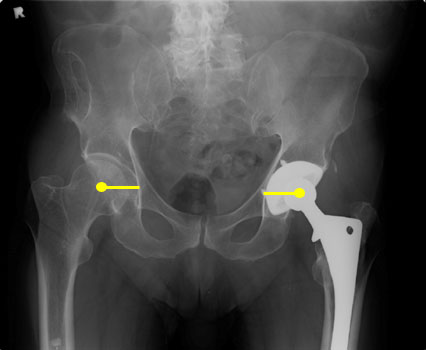

ACETABULAR COMPONENT

HORIZONTAL CENTER OF ROTATION

Distance from center of the femoral head to teardrop (or other identifiable

landmark) should be equal bilaterally.

The iliopsoas tendon should pass just lateral to the center of the femoral

head and helps to keep the hip proper alignment. Excessive lateral positioning

of the acetabular component results in the iliopsoas tendon crossing medial to

the femoral head, placing the patient at risk for dislocation.